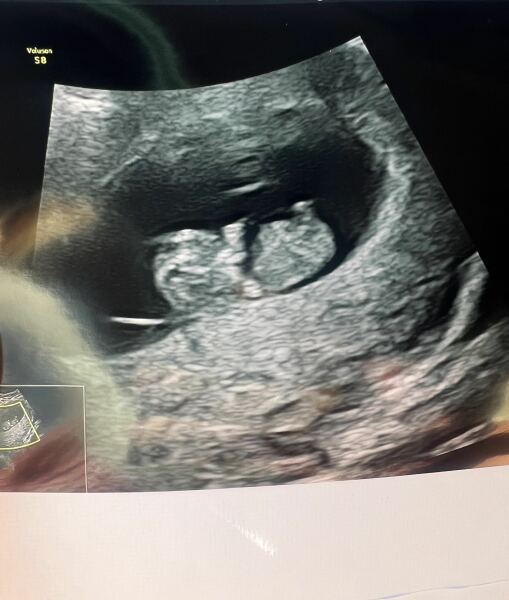

I was soo nervous. Mine was at 9:30 this morning.

All good 🎉 baby is measuring the right size (9w4d) had a heartbeat etc. it’s got little arm & leg buds now and looking more like a baby!

starting to look like a baby 😍

4w5d test still not dark solid

@whatdoyouthink123456ohhhh look!!! Adorable 🥰

@CharlotteRaethanks 🥰 it’s nice to see the development. It’s crazy how much they change in 2 weeks